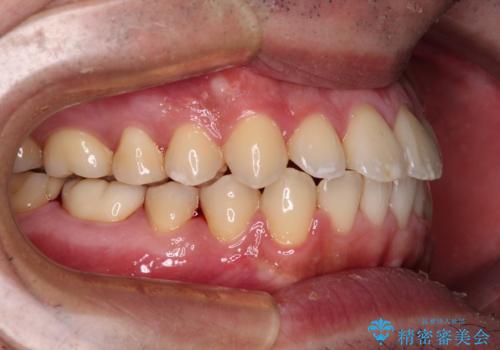

- 前歯のデコボコを治したいとのことで来院された患者様です。

できる限り楽して、短期間で治したいとのことで、ワイヤー装置にて矯正治療を行うこととしました。